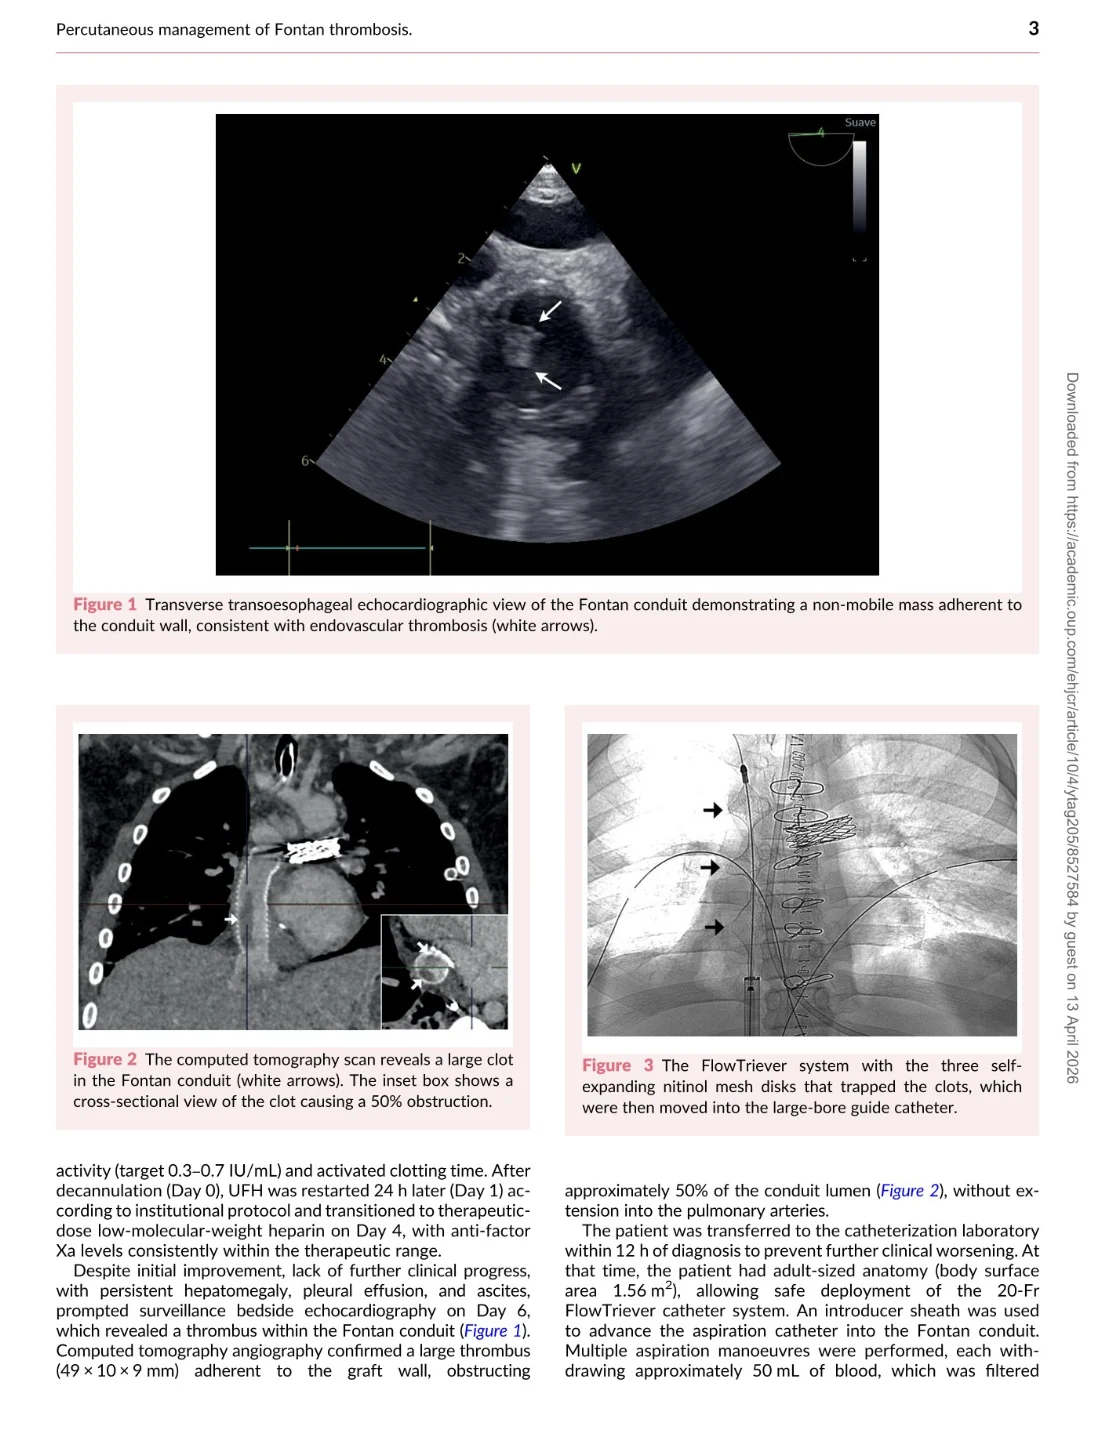

‘Percutaneous intervention for extensive thrombosis after the Fontan procedure in a 14-year-old’

A challenging case of Fontan conduit thrombosis managed with an innovative catheter-based thrombectomy approach, avoiding thrombolysis or redo surgery and achieving a great outcome.

Title: Case report of percutaneous intervention for extensive thrombosis after the Fontan procedure in a 14-year-old

Authors: David Ferri-Rufete, Juan Carretero Bellón, Fredy Hermógenes Prada Martínez, Federico Xavier Zarco Contreras, Joan Sanchez-de-Toledo